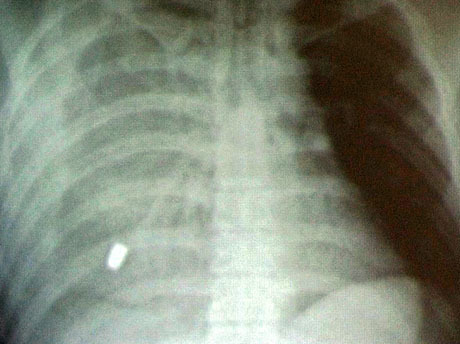

A szakember ugyanakkor hangsúlyozta, hogy azokban a térségekben, megyékben továbbra is kötelező lesz szűrni, amelyekben 100 ezer lakosból 25-nél több a tuberkulózisos (tbc-s) betegek száma.

A rendelettervezet értelmében a rizikócsoportoknál - ilyenek a hajléktalanok vagy a rossz szociális helyzetben lévők - vezetnének be célzott szűréseket - mondta a főosztályvezető. Hozzátette: az ilyen szűrések sikerességében fontos szerep hárul a hajléktalan-ellátásban részt vevő szervezetekre, a védőnőkre, a családsegítő hálózatra, de a rendelet lehetővé tenne hatósági intézkedést is. Az úgynevezett népegészségügyi körözésben érintetteket tehát akár a rendőr is bekísérhetné a kijelölt tüdőszűrő állomásra.

A rendelettervezet szerint továbbra is kötelező marad a tbc-vel fertőzöttek közvetlen környezetében élőknek a szűrése, de ezt a kört is kibővítenék: nemcsak a közvetlen családtagokat szűrnék, hanem például a munkatársakat is.

Szintén kötelező elem maradna a foglalkozás-egészségügyi szempontból elrendelt szűrés, de a tervezett jogszabály előírná például a büntetés-végrehajtásban dolgozók vagy a börtönben lévő, börtönbe vonulók szűrését is.